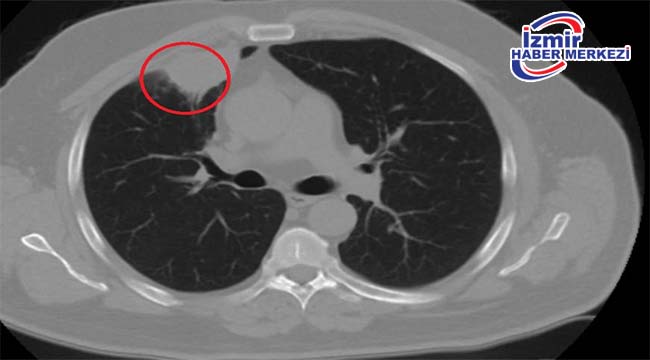

Kent dışında çalışan N.T.’nin, göğüs ağrısı şikayetiyle gittiği hastanede çekilen tomografisinde sağ akciğerinde 4 santimetre çapında tümör tespit edildi. Kanser olabileceği şüphesiyle yapılan ileri tetkikler sonrası N. T.’ye akciğer kanseri teşhisi kondu ve acil ameliyat kararı verildi.

– Hastamız, çalıştığı başka bir kentte göğsünden darbe alıyor ve ağrıları geçmeyince bir üniversite hastanesine başvuruyor. Burada hastaya bir akciğer grafisi çekiliyor. Sağ akciğerinde bir kitleye rastlanıyor. Daha sonra hastaya, bir akciğer tomografisi çekiliyor ve göğüs cerrahisi için önemli büyüklükte olan 4 santimetre çapında, akciğer kanserine benzer özellikte radyolojik bulgular olan bir kitle tespit ediliyor. Daha sonra hastaya yapılan ileri tetkiklerde akciğer kanseri teşhisi konuluyor. Hastaya bir cerrahi planlanıyor.